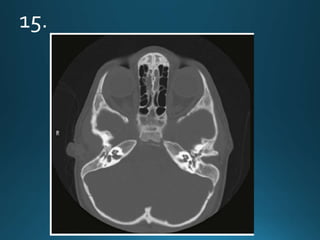

11.

External auditory canal atresia (EACA) is characterised by complete or incomplete

bony atresia of the external auditory canal (EAC)

Findings in the middle ear are variable and the inner ear and inner auditory canal are

typically normal

number of syndromes are associated with external auditory canal atresia 2.These

include:

• Crouzon syndrome

• Treacher Collins syndrome

• Goldenhar syndrome

• Pierre Robin syndrome

External auditory canalatresia (EACA) is characterised by complete or incomplete bony atresia of the external auditory canal (EAC) Findings in the middle ear are variable and the inner ear and inner auditory canal are typically normal number of syndromes are associated with external auditory canal atresia 2.These include: • Crouzon syndrome • Treacher Collins syndrome • Goldenhar syndrome • Pierre Robin syndrome